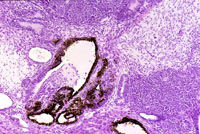

Ovarian teratomas that metastasize to the liver are uncommon in mice.

A clearly demarcated ovarian teratoma in the liver; a higher magnification shows pigmented epithelial-lined glands, glandular structures without pigment, undifferentiated epithelial cells, and mesenchymal tissue.